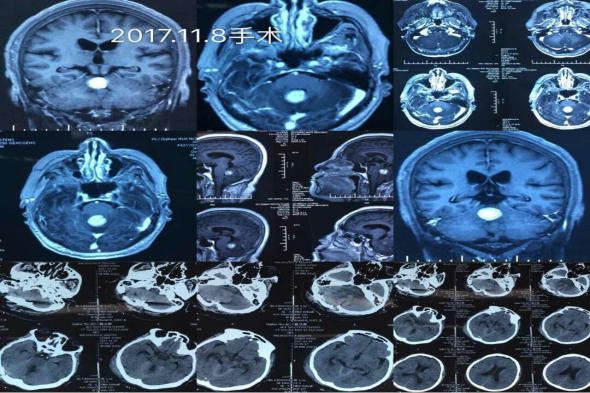

患者徐某,63岁,3周前老人突然出现站立不稳,走路向一侧偏斜,并有头晕不适等症状,家人立即带老人到当地医院就诊,以脑血管病对症治疗,但是症状不见好转。之后慕名来到我院入住神经外二科,经过一系列的CT、核磁检查,在脑干、小脑蚓部发现了一处占位性病变,脑桥粘连并明显受压,随时有生命危险。而且患者的肿瘤位于脑干、位置深,稍有不慎即可造成致死致残,手术风险极高。经过完善的术前准备后,11月8日,在科室主任吴卫东的带领下进行手术,无影灯下,生命禁区,手术刀在世界上最精密、最复杂的脑干神经网中精准游走,丝毫不差,采用后正中入路,在显微镜下有条不紊的分离、切开小脑蚓部,保护桥脑、仔细分离、逐块完全切除肿瘤,手术非常成功。术后患者意识清醒,无偏瘫失语、面瘫及共济失调等并发症,目前患者恢复良好。

术前、术后检查